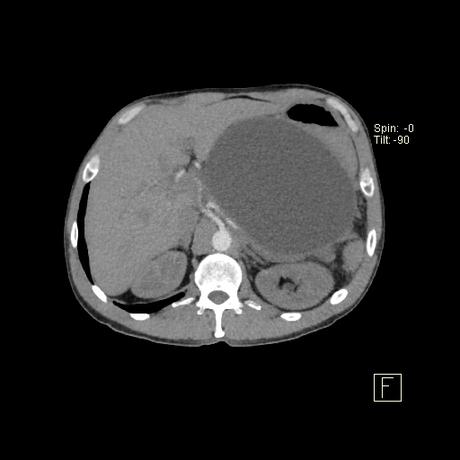

Los pseudoquistes pancreáticos se encuentran con frecuencia en el seguimiento por imágenes de la pancreatitis y pueden ser asintomáticos en sí mismos durante algún tiempo. Las presentaciones atribuibles a un seudoquiste incluyen:

producen por la alteración de la estructura del conducto pancreático con la consiguiente pérdida y acumulación de jugo pancreático que da lugar a una necrosis grasa hemorrágica. No están revestidos por epitelio (por lo tanto, “pseudoquistes”), sino que una reacción inflamatoria grave da como resultado la encapsulación del quiste por tejido de granulación fibrosado. Esto suele tardar de 4 a 6 semanas 8,9 . En aproximadamente el 50% de los casos, el quiste conserva una comunicación con el conducto pancreático 2 . Estos quistes son más problemáticos de tratar y es más probable que reaparezcan.